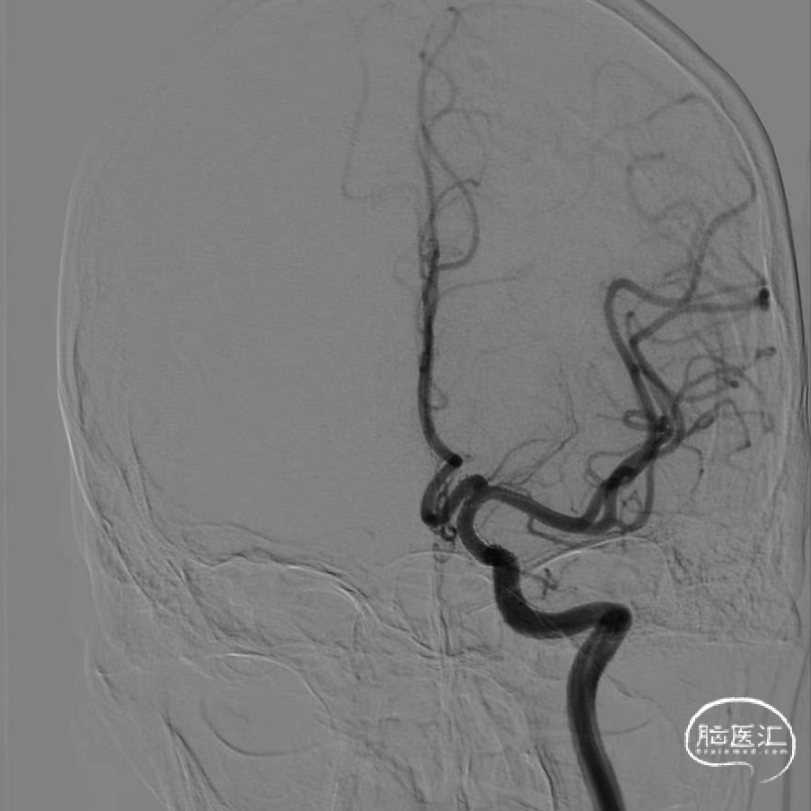

术中DSA造影:左侧颈内动脉正、侧位及3D造影,显示左侧颈内动脉海绵窦段动脉瘤,左侧后交通动脉起始端壶腹膨大。

术中DSA造影:左侧颈内动脉3D造影,显示左侧颈内动脉海绵窦段动脉瘤,载瘤动脉远端直径3.36mm;近端直径4.20mm。

术中DSA造影:右侧颈总动脉正、侧位造影。

术中DSA造影:左侧椎动脉正、侧位造影。